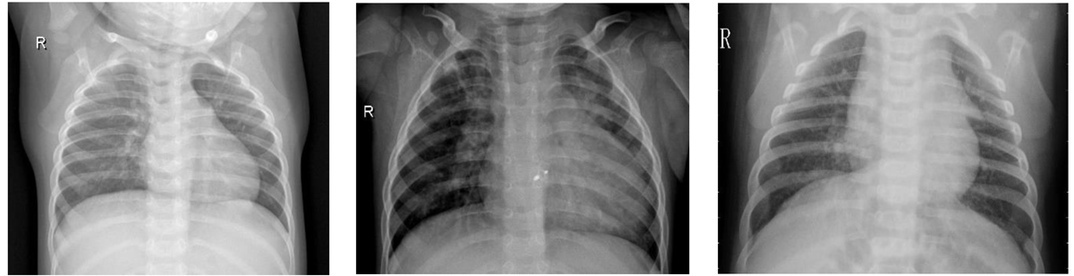

ИИ может определять расу людей по рентгеновским снимкам, и ученые в шоке

Новые исследования показывают, что нейросети способны определить расу любого человека по его рентгеновским снимкам. Что было бы совершенно невозможно для врача-человека, смотрящего на те же изображения.

Группа ученых из США, Тайваня и Канады опубликовала свою работу в журнале The Lancet Digital Health.